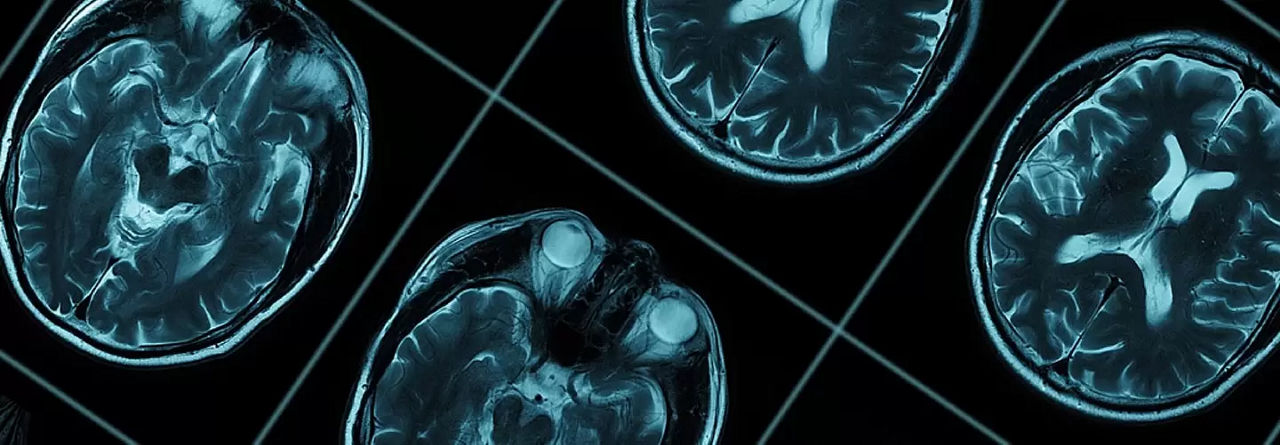

Неврология — это отрасль науки, изучающая структуру, заболевания и физиологию нервной системы. Обычно предметом ее исследований является головной мозг, ствол головного мозга, спинной мозг и прилегающие структуры. Она включает терапевтические практики, отличающиеся от диагностики и стандартного лечения.

Неврология — это наука, изучающая нарушения нервной системы, в том числе головной мозг, кровеносные сосуды, нервы и мышцы. Этот термин состоит из слов «нейрон», что означает «нерв», и «логия», что означает «исследование». В целом, неврология включает следующие области исследования:

Неврология — это медицинская область, которая занимается головным мозгом и его заболеваниями. Неврология, занимающаяся в основном такими заболеваниями, как инсульты, эпилепсия, болезнь Альцгеймера, деменция, болезнь Паркинсона, расстройства памяти и сна, взаимодействует с другими специальностями.

Область неврологии — это отрасль науки, изучающая такие отделы, как головной мозг, спинной мозг и периферические нервы, а также заболевания мышц; в ней используются методы лечения, отличные от хирургического вмешательства. Эпилепсия, болезнь Паркинсона, болезнь Альцгеймера, мигрени, а также опухолевые заболевания — наиболее известные и широко встречающиеся заболевания среди неврологических расстройств, с которыми обращаются в отделения неврологии в больницах.